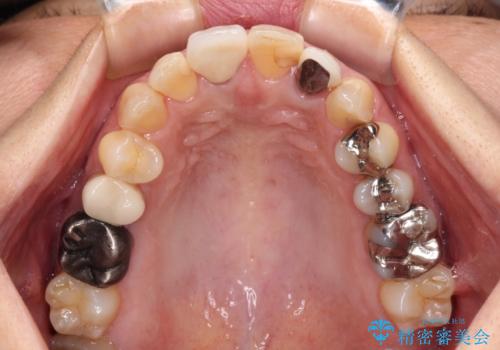

- 保険診療でのクラウンが変色してしまったとのことで来院された患者様です。

根管治療がされていなかったため、まずは根管治療を行い、その後オールセラミッククラウンにて補綴することとしました。

左上の歯も歯肉縁部分にメタルの色が見えており、合わせて治療することをお勧めしましたが、今回は1歯のみを治療することとしました。